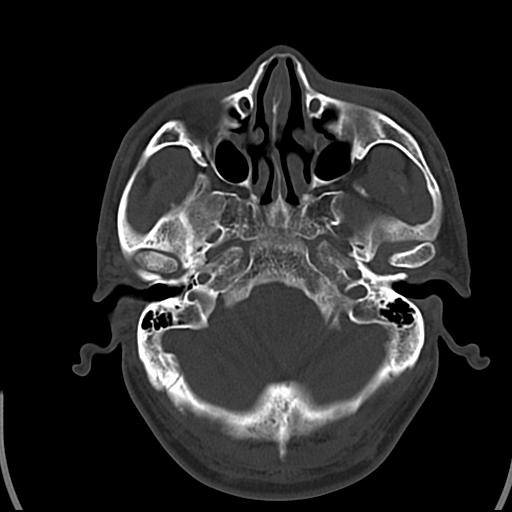

头皮下高密度结节影???临床上在老年男性比较常见。大家看看是什么?成因是? 本例患者,男性,51岁。外伤来诊。无染发史及发根植入史。